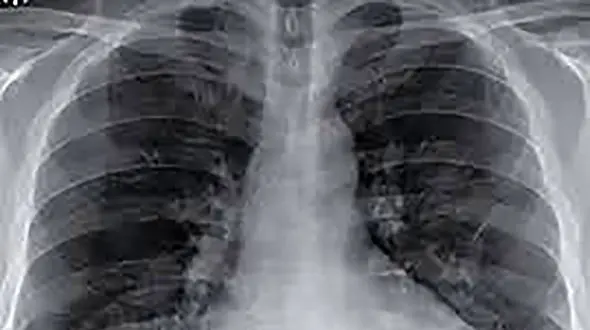

سلامت رکنا : پزشکان متخصص بیماریهای عفونی به سوالات رایج درباره درگیری ریه ها در بیماری کرونا پاسخ داده اند.